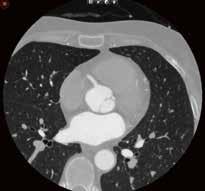

Weniger Dosis und bessere Bilder: AiCE im Bereich der Thorax- und Abdomendiagnostik

Als im Clemenshospital Münster die Entscheidung zur Anschaffung eines zweiten CT-Scanners getroffen werden sollte, fiel die Wahl schnell auf den Canon CT Aquilion Prime SP, insbesondere da zuvor schon lange gute Erfahrungen mit dem Betrieb des Canon Aquilion ONE gemacht worden waren.

Als dann kurz darauf noch AiCE nachgerüstet wurde, stieg der Wert der Investition durch die Möglichkeiten der Dosisreduktion und Bildqualitätsverbesserung nochmals an. In vielen Bereichen der CT-Diagnostik sind die neuen, KI-basierten Rekonstruktionen im Clemenshospital nun fester Bestandteil der Standardprotokolle. Vor allem die rasche Implementierung und der nur wenig größere

Zeitaufwand für die Bildrekonstruktion fielen hierbei äußerst positiv auf. Der Mehrwert lässt sich leicht anhand einiger Beispiele aus dem klinischen Alltag belegen. Zusammenfassend bieten sich mit AiCE deutliche Vorteile: zum einen bei der Bildqualität und somit auf dem Weg zur richtigen Diagnose zum anderen durch die Dosisreduktion auch im Bereich der Patientensicherheit.

Fall 1:

Biphasische Abdomen-CT bei einer deutlich adipösen Patientin. Hier lässt sich sowohl Dosis sparen als auch die Qualität der Rekonstruktionen verbessern. Beispielsweise findet sich deutlich weniger Bildrauschen, insbesondere im Bereich der parenchymatösen

Fall 2:

Portalvenöse Abdomen-CT. Auch hier ist die Dosis am Aquilion Prime SP mit AiCE geringer, zudem auch hier geringeres Bildrauschen mit sehr guter Abgrenzbarkeit, beispielsweise von Leberläsionen.

Abb. 1 a: biphasische Abdomen-CT, Canon Aquilion Prime, Rekonstruktion: AIDR 3D; DLP 1003,6 mGy × cm / 18,1 mSv. Abb. 2 a: biphasische Abdomen-CT, Canon Aquilion Prime, Rekonstruktion: AIDR 3D; DLP 1003,6 mGy × cm / 18,1 mSv. Abb. 1 b: biphasische Abdomen-CT, Canon Aquilion Prime, Rekonstruktion: AiCE; DLP 716,5 mGy × cm / 12,9 mSv. Abb. 2 b: biphasische Abdomen-CT, Canon Aquilion Prime, Rekonstruktion: AiCE; DLP 716,5 mGy × cm / 12,9 mSv. Oberbauchorgane.

Fall 3:

Thorax-CT im Rahmen einer Lungenkrebsfrüherkennungsstudie. Die Voruntersuchung lag als externe kontrastmittelgestützte Thorax-CT vor. Bei der dosisoptimierten Low-Dose-CT liegt die Strahlenexposition nur noch im Bereich von zwei konventionellen Röntgenaufnahmen des Thorax, die Bildqualität ist für die Fragestellung nach Herdbefunden aber dennoch eindeutig ausreichend, selbst interstitielle Lungenveränderungen lassen sich hier noch beurteilen.

„KI-basierten Rekonstruktionen im Clemenshospital nun fester Bestandteil der Standardprotokolle.“

Prof. Dr. med. Johannes Weßling Zentrum für Radiologie, Neuroradiologie und Nuklearmedizin Abb. 3 a: kontrastmittelgestützte Thorax-CT, externe Untersuchung; DLP 216,0 mGy × cm / 3,9 mSv. Abb. 3 b: dosisoptimierte Low-Dose-Thorax-CT, Canon Aquilion Prime SP, Rekonstruktion: AiCE; DLP 13,9 mGy × cm / 0,25 mSv.

Low-Dose-Thorax-CT als Verlaufskontrolle bei Lungenkarzinom unter Immuntherapie. Aus der Anfangsphase der Implementierung von AiCE im klinischen Alltag zeigt sich bei vergleichbarer Dosis eine bessere Bildqualität mit besserer Detailauflösung im Bereich des Lungenparenchyms, hier im Bereich der strahligen Ausläufer des Tumors und an den direkt angrenzenden Bronchialstrukturen gut zu erkennen.

Fall 4: Fall 5:

Einer der ersten Patienten, die nach der Installation der AiCE-Algorithmen untersucht wurden. Hier wurde zum Vergleich aus derselben Untersuchung jeweils eine Rekonstruktion mittels AIDR 3D und eine Rekonstruktion mit AiCE angefertigt. Auch hier fällt die bessere Detailauflösung, beispielsweise im Bereich der Interlobulärsepten oder der Emphysembullae, auf. //

Abb. 5 a: Low-Dose-Thorax-CT, Canon Aquilion Prime SP, Rekonstruktion: AIDR 3D; DLP 115,8 mGy × cm / 2,1 mSv Abb. 4 a: Low-Dose-Thorax-CT, Canon Aquilion ONE, Rekonstruktion: AIDR 3D; DLP 55,1 mGy × cm / 1,0 mSv Abb. 5 b: dieselbe Untersuchung, Rekonstruktion: AiCE Abb. 4 b: Low-Dose-Thorax-CT, Canon Aquilion Prime SP, Rekonstruktion: AiCE; DLP 65,7 mGy × cm / 1,2 mSv